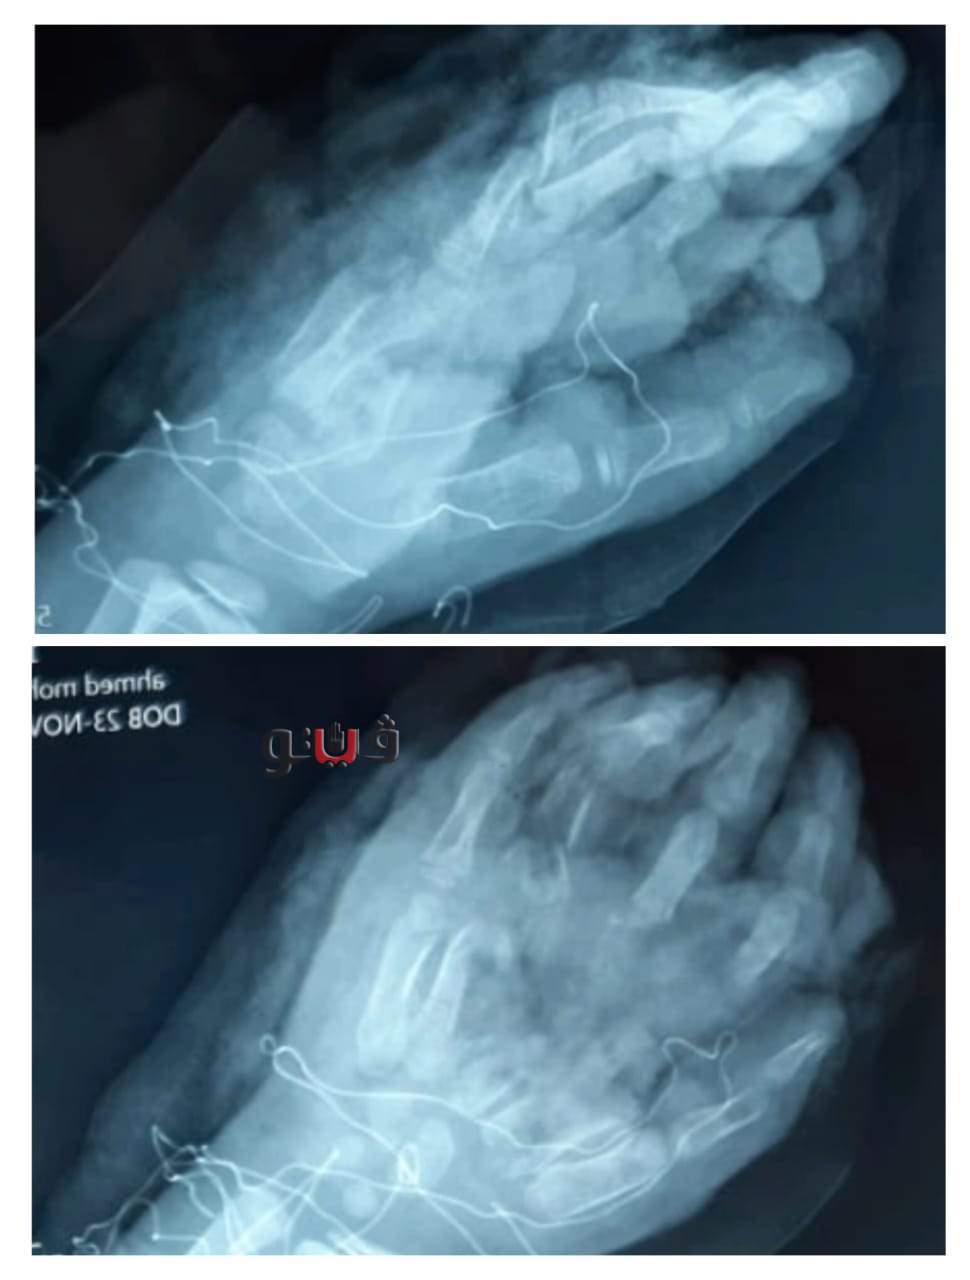

أعلن الدكتور سعد مكي وكيل وزارة الصحة بالدقهلية، عن نجاح فريق طبي بمستشفى المنصورة العام الجديد في إنقاذ يد طفل يبلغ من العمر 7 سنوات من البتر إثر حادث ماكينة.

وأسفر الحادث عن تهتك شديد في الجلد والأنسجة الرخوة مع فقدان للأوتار الباسطة للأصابع وأجزاء من الجلد والعظام في اليد اليمنى مع اعتلال بالدورة الدموية في الأصابع .

وأكد وكيل وزارة الصحة بالدقهلية أنه تم التدخل الطبي السريع تحت مخدر عام وتم تنظيف الجرح والأنسجة المتهالكة وتثبيت الكسور وعمل رقعة عظمية من عظمة الساق (الشظية) واستخدامها بدلا من عظام اليد المتهتكة والمفقودة، وعمل سديلة جلديه من البطن لتغطية العظم المكشوف وتم حجز الطفل بالقسم تحت الرعاية والمتابعة تمهيدا للمرحلة الثانية من الجراحة.

وإطمأن وكيل صخة الدقهلية على ان الحالة العامة للطفل مستقرة وحالة اليد جيدة.